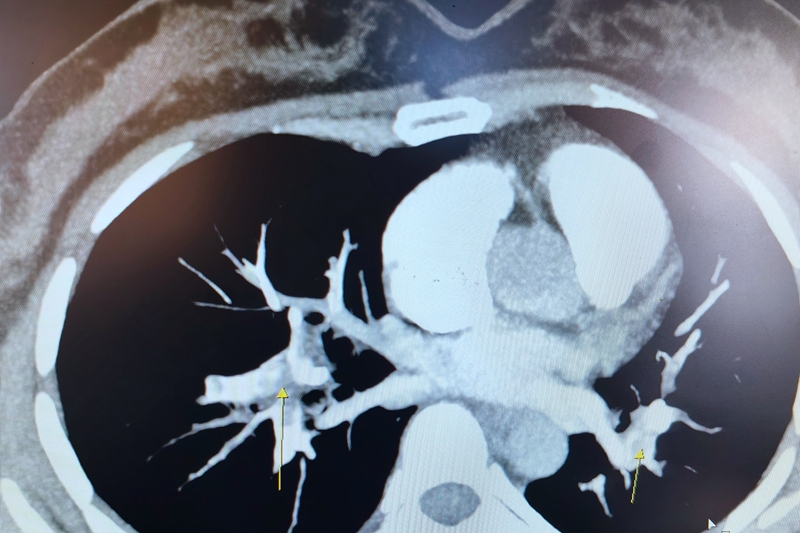

【CT影像】

“急诊CT提示,患者肺部双侧与主干血管均有不同程度的栓塞,我们立刻采取了吸氧、抗凝等治疗。”呼吸与危重症医学科主治医师王剑解释,彭女士是因久坐导致下肢深静脉血栓,引起急性肺栓塞、呼吸衰竭。